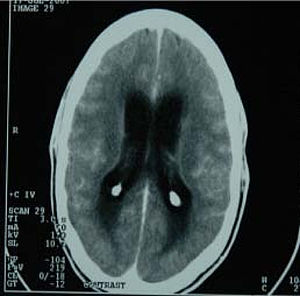

CT scan showing tuberculous meningitis